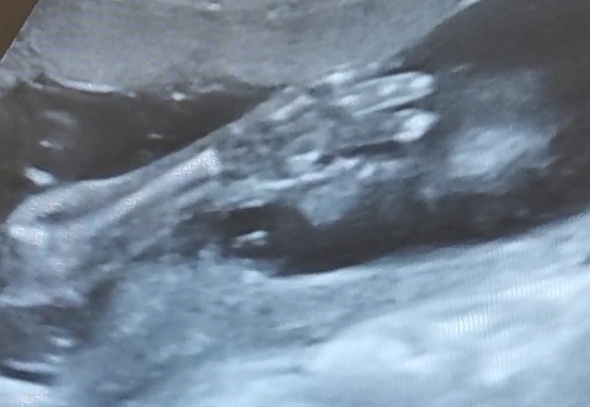

Ja po wczorajszej wizycie 🙂 mały miś pięknie rośnie 🥰🥰🥰